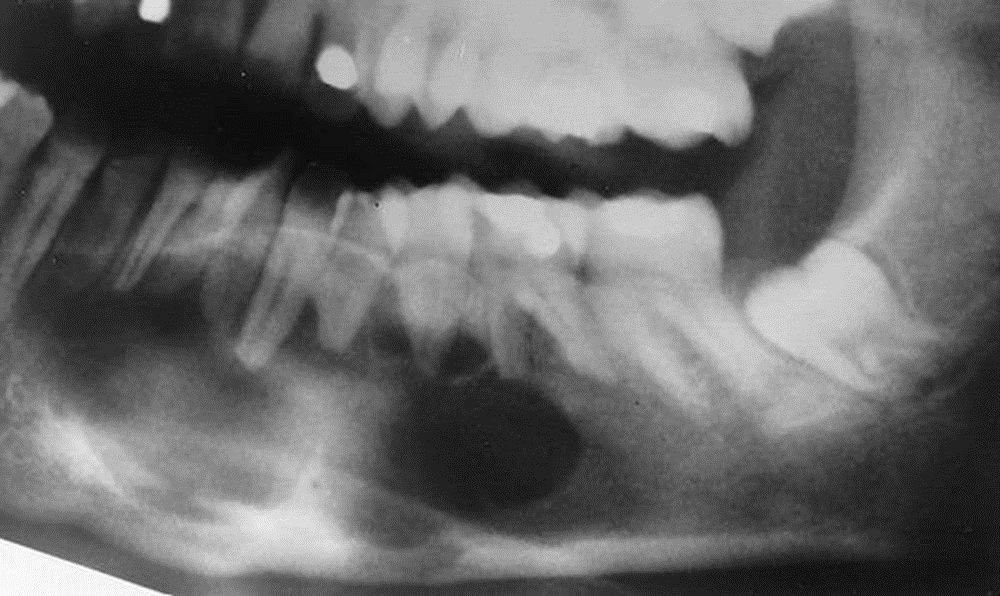

4. This 72-year-old woman presented with loose 20-yearold dentures and slight intermittent pain under the lower denture. She stated she had her teeth extracted because of severe untreated caries and abscessed teeth. The radiolucent lesion was detected on a radiograph of the painful area.

What is your diagnostic impression?